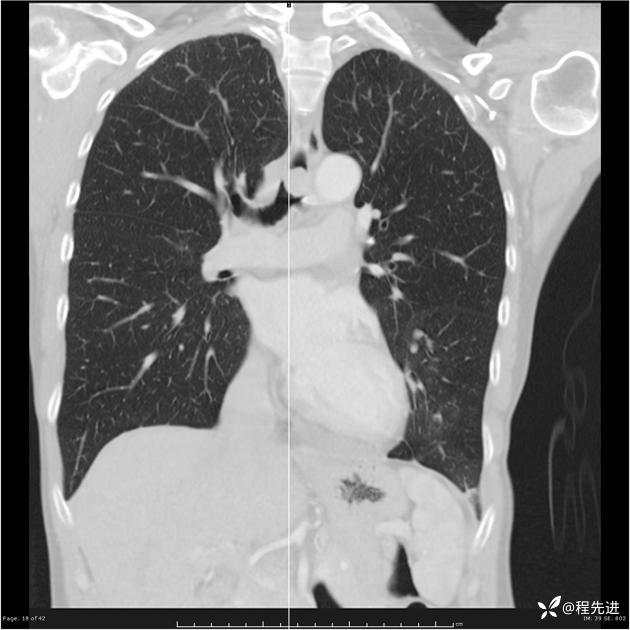

病例女,53岁,气管、左主支气管、下叶支气管内结节,乳头状瘤?期待你的精彩解读

女,53岁

乳头状瘤?